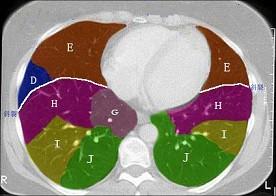

结合肺段模式心室层面(见图),选出右肺上叶的组成 ( )A、A+B+C+DB、A+B+C+D+EC、A+BD、A+B+CE、A

问题 结合肺段模式心室层面(见图),选出右肺上叶的组成 ( )

选项 A、A+B+C+D B、A+B+C+D+E C、A+B D、A+B+C E、A

答案 D